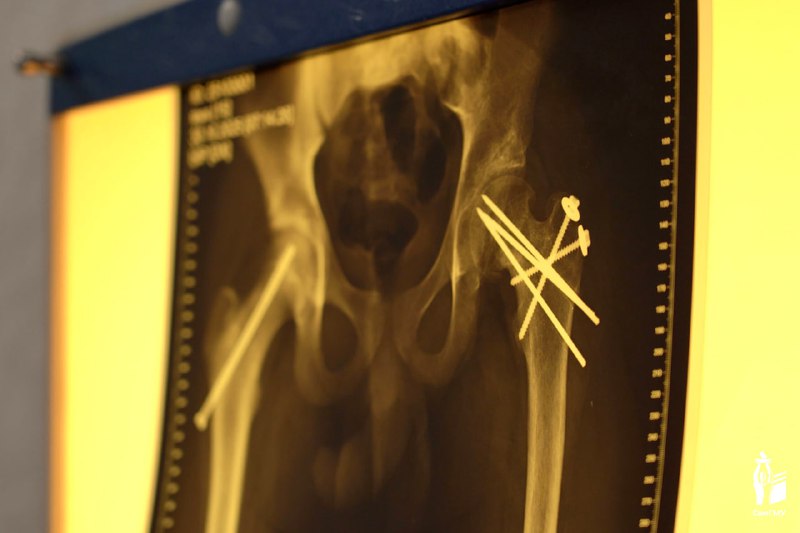

В ходе операции врачи СамГУ применили модифицированную методику Данн. Это сложнейшая техника при которой головку бедра снимают и возвращают в правильное положение, стараясь не повредить единственную питающую артерию.

Вчера состоялся заключительный этап лечения. Хирурги удалили Егору установленные на первом этапе металлоконструкции. После реабилитации подросток сможет полноценно наступать на ногу.